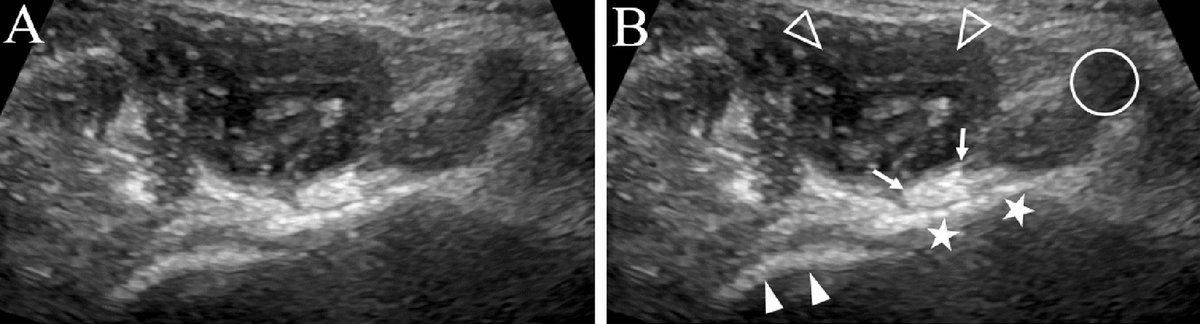

Ultrasound-guided preoperative skin-marking for deep inferior epigastric perforator flap surgery dlvr.it/TDdS6b